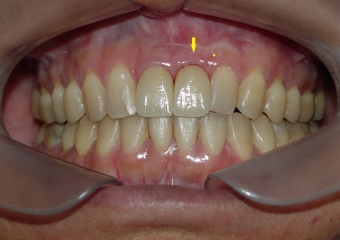

Imagens iniciais com elemento 21 comprometido

Imagem de 3 meses de controle